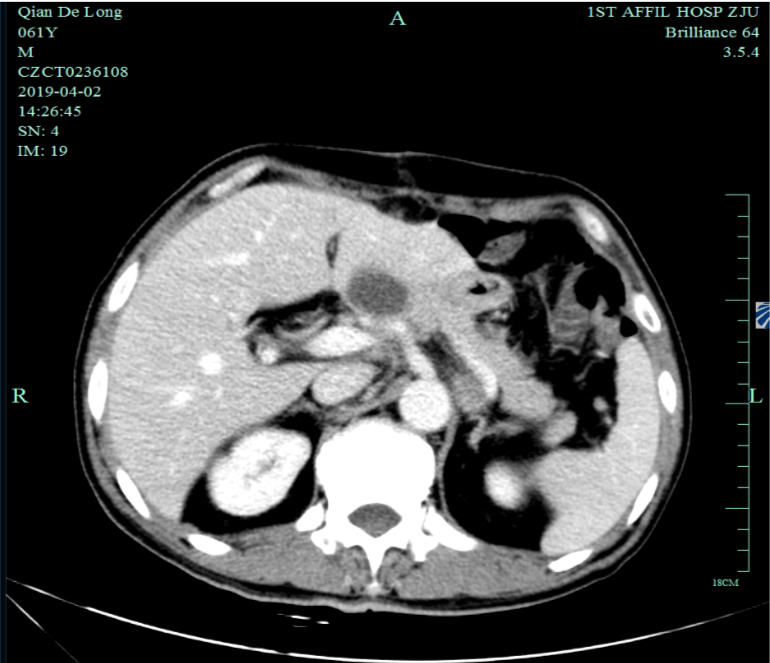

既往史(续):全腹部CT平扫+增强提示胃贲门部及体部胃壁增厚,结合临床考虑胃癌伴胃周及腹膜后多发淋巴结转移;肝脏多发血管瘤。

入我院后全面进行评估(2019.4):全腹部CT平扫+增强评估提示腹膜后,胰腺周围多发淋巴结增大,淋巴结转移考虑。

2019-4-2至2019-6-5行SOX+赫赛汀 q3w 4周期联合化疗:具体为奥沙利铂220mgD1、替吉奥3# BID D1-14、赫赛汀400mg(首次)+300mg。

一线化疗疗效评估(2019.6 vs 2019.4):胃癌术后改变。影像评估CR。